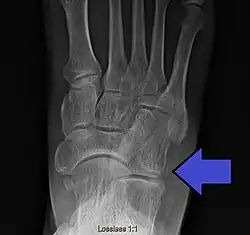

| Avulsion fracture of the right cuboid bone of the foot | |

A cuboid fracture is a fracture of the cuboid bone of the foot. Diagnosis is by X-ray imaging, magnetic resonance imaging, or bone scan.[1] Treatment may be conservative or involve surgery, depending on the type of fracture.[1] They are rare.[1]

If the cuboid bone is broken, then it is common for other bones in the foot to be broken or dislocated as well.[2] Cuboid fractures are associated with Lisfranc injuries.[2]